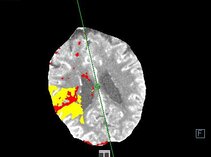

Spezielle, sogenannte „dynamische“ Untersuchungen können beispielsweise beim Schlaganfall sehr gut das betroffene sowie das potentiell rettbare Gewebe zeigen, um den Patienten zeitnah einer Therapie zuzuführen.